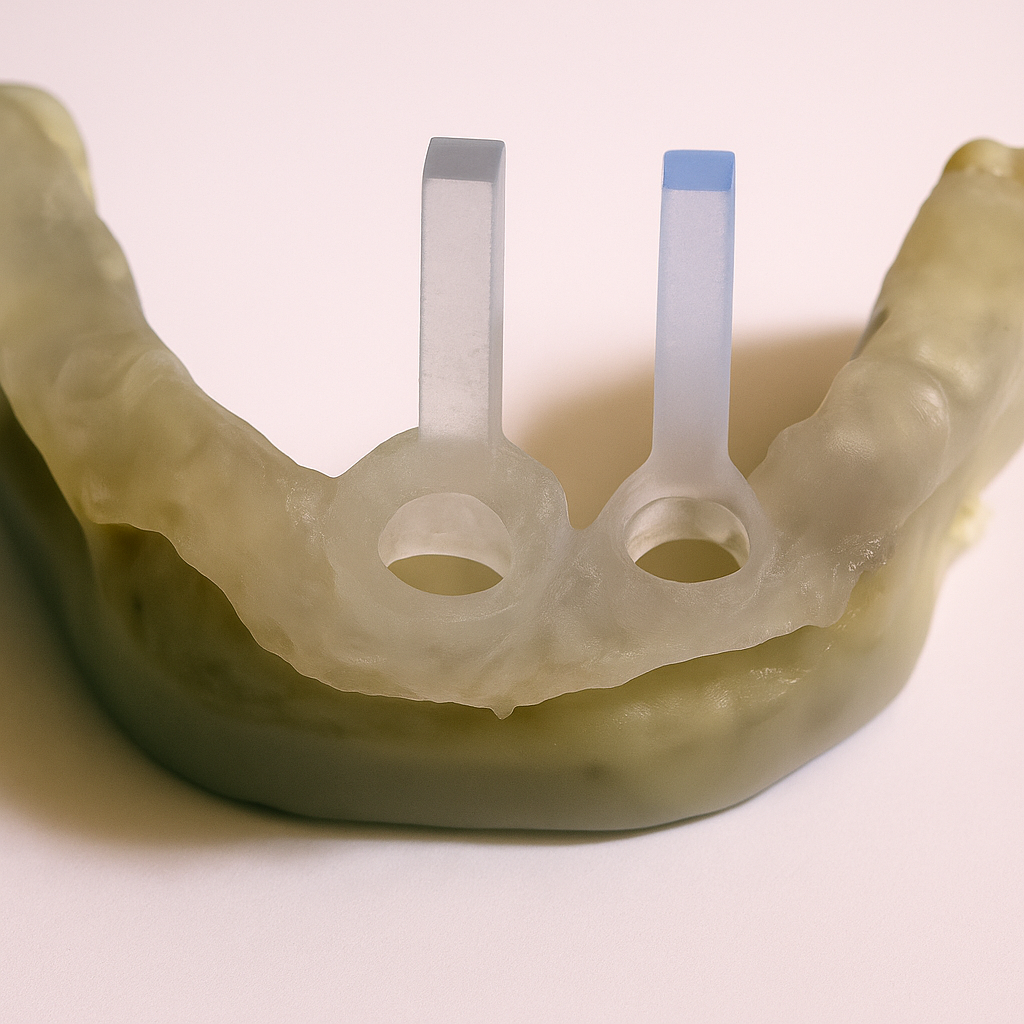

Implant axes materialized

Visualization of implant axes in reality from two angles, accurately confirming the software planning.